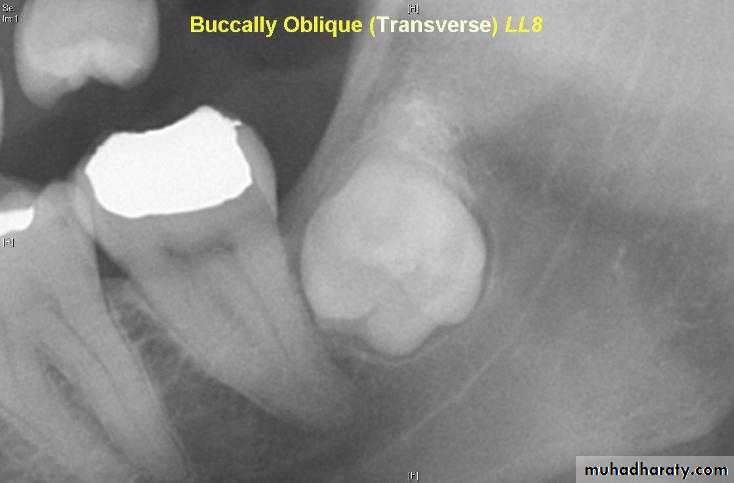

a –the tube shift techniqueUses two periapical radiographs, shifting the tube horizontally between exposures.

If the unerupted teeth moves in the same direction in which the tube is shifted, its located on the lingual or palatal side

A facial or buccally located tooth moves in the opposite direction to the tube shift.

b – periapical and occlusal film

Uses the periapical radiograph taken with standard technique and an occlusal radiograph to give different views of the impacted tooth